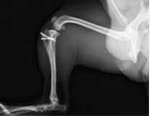

症例1

パピヨン×マルチーズ(10ヶ月齢、雌)

グレードⅢ 外科手術

- 【初診時症状】

- お散歩時跛行し、以降頻繁に外れるようになった

- 【手術】

- 脛骨粗面転位術、関節包縫縮を実施

- 【経過】

- 同居犬がおり、安静の維持が難しいため、術後2週間入院。術後4週間で屋内での運動制限を徐々に解除、8週間でお散歩の距離を少しずつ伸ばしていくも歩行問題なし。術後しばらくは右後肢の術創を気にして舐めていたが経過観察期間に徐々に消失。現在は制限なく生活。